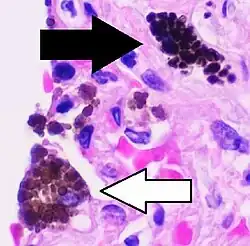

Anthracosis Black-brown granules Interstitium (perivascular)

• Age and urban dwelling.[2]

• Coal workers[3]

Black arrow shows interstitial anthracotic pigment. Nearby macrophages (white arrow) can be presumed to contain anthracotic pigment.